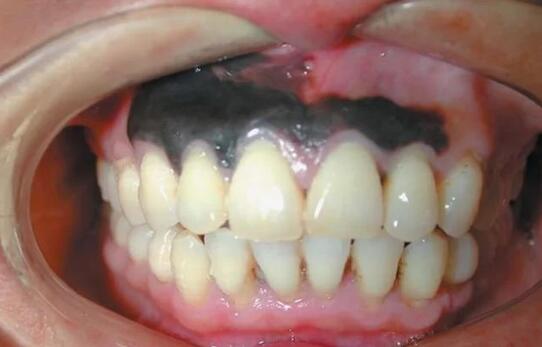

很多人都会关注牙齿,虽然只是关注有没有变黄。但实际上,说出来你可能不信,我们的牙龈,是会得癌的,而且有很明显的特征:牙龈上长有黑斑,也许就是黑色素瘤。

牙龈上的黑斑不会痛,也不会痒,导致很多人都以为它是牙龈炎而忽略掉。到后面才发现,这种并不是牙龈炎,而且随着时间,嘴角会流血不止,黑斑块也会慢慢扩散,这个时候,已经晚了,有很大可能是恶性黑色素瘤。

目前,据已知的医学统计显示,黑色素瘤的主要征兆是黑痣、黑色斑块、如果在有这两个的前提下,再出现出血,瘙痒,压痛,面积扩大,硬度增加,溃疡等情况,要警惕癌变了。

癌变的时候,黑色素瘤会在皮肤下面形成肿块,然后就向四面八方扩散,并出现星状的黑斑或小结节。同时,该区域的淋巴结肿大,病情一旦发展至晚期,常见的会转移到肺、肝、骨骼、脑等地方。